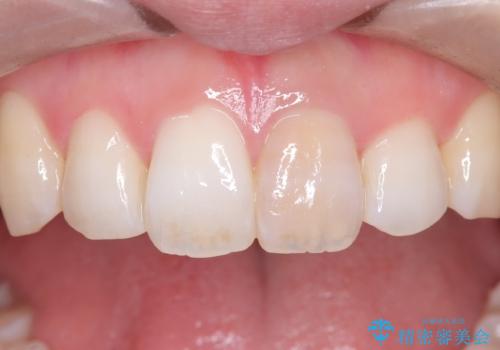

前歯の気になる変色を解消。再根管治療とオールセラミックで自然な美しさへ

担当医 河口智英